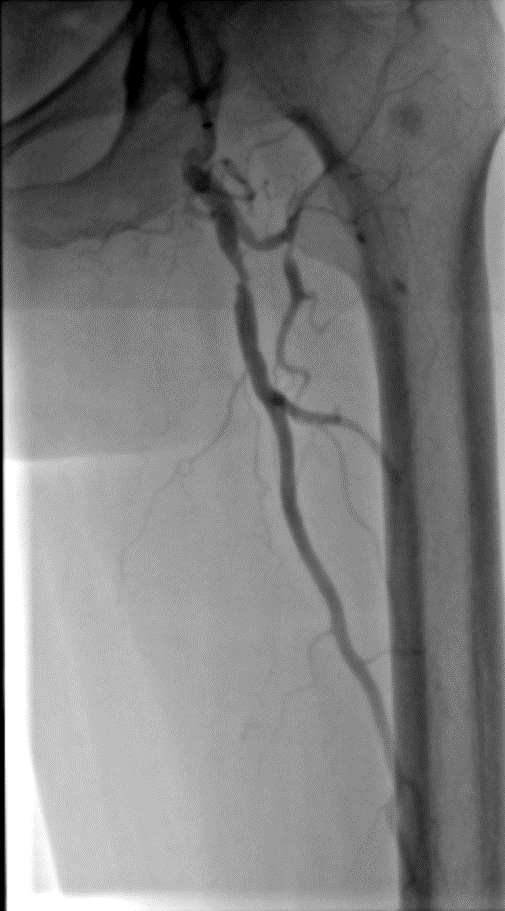

★ Case 1

noproximal stump in SFA,>250mm

★ Case 2

significantdistal collaterals